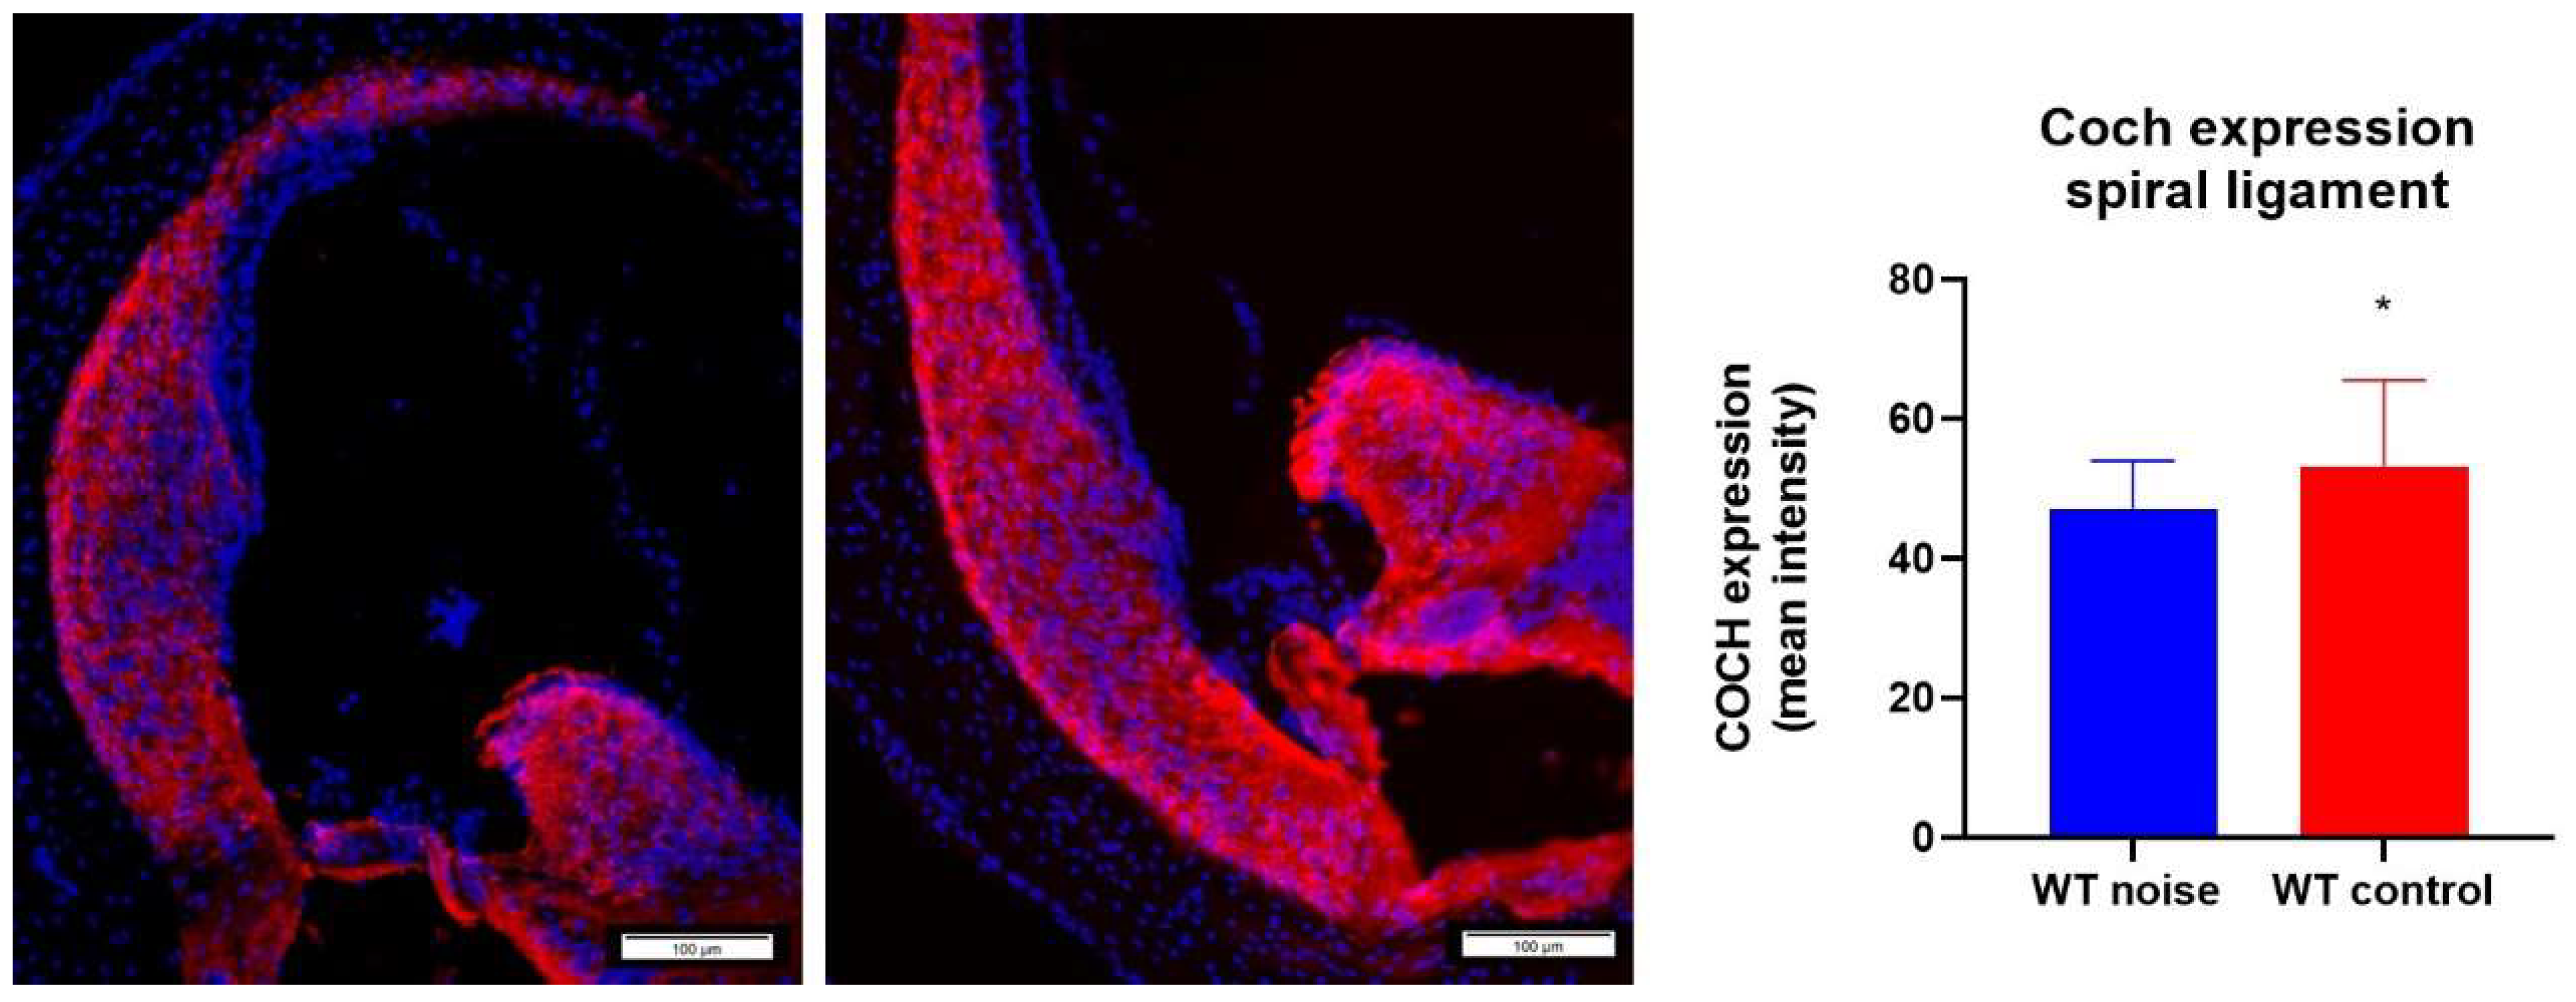

2.7. Noise Trauma Reduces Cochlin Immunoreactivity in the Spiral Ligament

3.5. Coch Expression